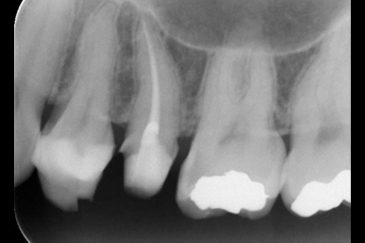

CASE 2

BEFORE

AFTER

基本情報

| 年齢・ 性別 |

40歳・男性 |

|---|---|

| 主訴 | 虫歯・左上6 |

| 治療 内容 |

左上6・根管治療 |

| 治療 期間 |

2回 |

| 治療費 | 保険診療 約3,000円 |

| リスク・ 副作用 |

神経を取ってもすぐに痛みが引かない可能性があります。 神経の治療の刺激により、数日痛み・腫れがでる可能性があります。 細く繊細な器具を使用するため、器具が破折する可能性があります。 複雑な神経の治療では、大学病院もしくは専門医による治療が必要となることがあります。 または抜歯になることもあります。 |